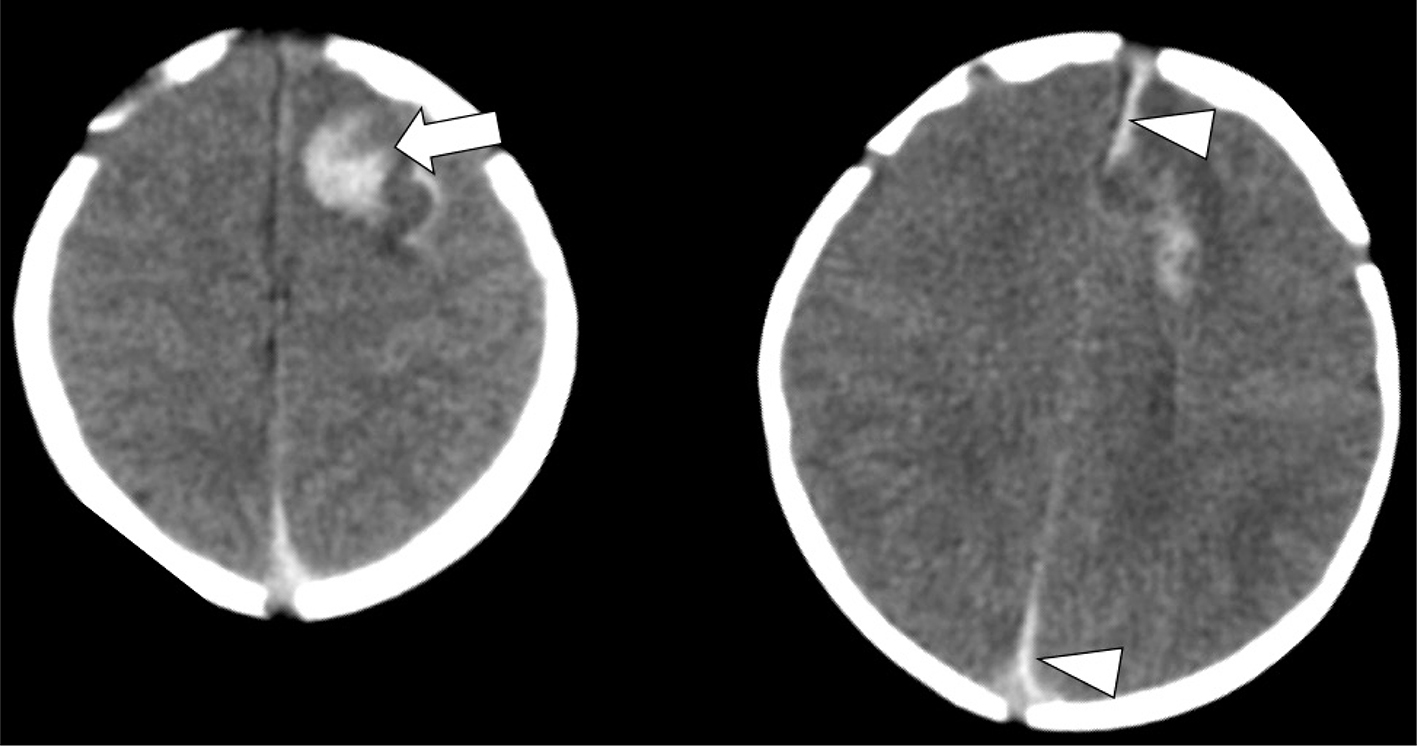

On MRI, acute infarcts demonstrate reduced diffusivity within minutes, exhibiting high signal on DWI and low computed diffusivity on ADC maps (Figure 5) (46). Diffusivity remains reduced for about 6 days, peaking at about 3 days, before pseudonormalization occurs, with diffusivity then increasing to above normal by the second week (4750). Timing of DWI changes can be affected by the age of the patient, size of the stroke, and how quickly collateral blood flow is recruited. DWI also detects early or pre-wallerian degeneration in infants (also referred to as “acute network injury”), characterized by injury to the antegrade white matter tracts following acute infarct and manifests as reduced diffusivity in white matter pathways affected by the infarction within a few days of the injury (Figure 5) (51). Common pathways affected by acute network injury include the corpus callosum, thalamus, and descending corticospinal tract. When seen along the corticospinal tracts, acute network injury is highly predictive of poor motor outcomes (52, 53).

Fig 5

Figure 5. Acute neonatal arterial ischemic infarction in a three-day-old girl with seizures. Axial DWI (A) and (B), and axial ADC (C) images show extensive area of reduced diffusion in the left MCA territory (arrows). Arrowheads (A, B, C) indicate pre-Wallerian degeneration in the posterior limb of the internal capsule and left cerebral peduncle along the corticospinal tract. D. 3D time-of-flight MRA shows abrupt absence of flow in the left MCA (arrow). Axial T2-weighted image (E) at 5-month follow-up shows extensive encephalomalacia and volume loss in the left MCA territory. Case courtesy of Dr. Tamara Feygin, Department of Radiology, Children’s Hospital of Philadelphia.